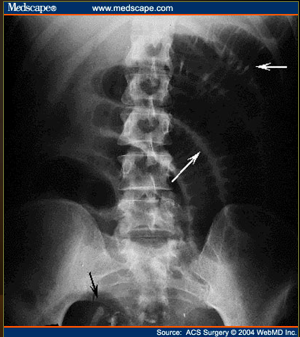

What do you see?

free air of large quantity

supine view

white arrows: crescents of air seen beneath each hemidiaphragm

blue arrows: both sides of the bowel wall are visible